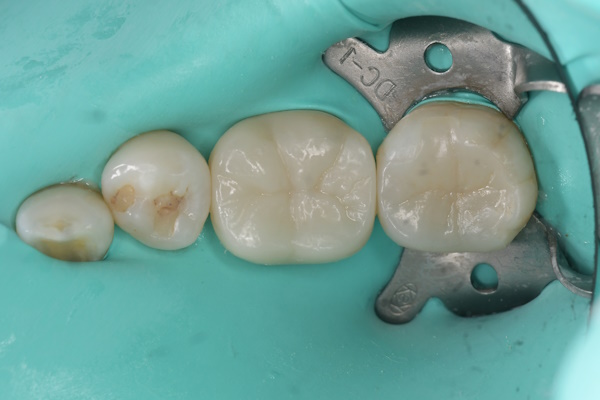

セラミック治療の治療例です。金属の使用を避けたいとのご希望から、メタルフリー治療を目的に来院されました。セラミックは生体親和性が高く、金属を使用しないため金属アレルギーのリスクが少なく、安心して使用できる素材です。当院にて虫歯治療を行い、セラミックによる修復を実施しました。通院回数の負担を考慮し、上下同時での治療をご希望されたため、同日に治療を行っています。接着の精度を高めるため、治療時にはラバーダムを使用しています。また、オキシガードは過酸化物と還元剤による化学重合反応により、歯科接着用レジンセメント表面の未重合層を硬化させる材料です。未重合層を空気から遮断することで確実な硬化を促します。

下顎

術前から術後までの治療の流れ

虫歯処置後

エッチング後

オキシガード使用後

セット後